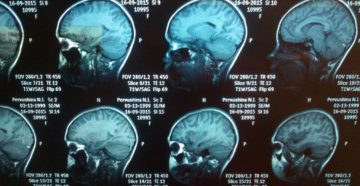

Расшифровка МРТ головного мозга: онлайн, норма, патология | Второе мнение Киста сфеноидальной пазухи Одиночное образование…